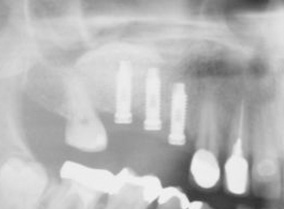

שתלים כתחליף לשיניים חסרות

השתלת שיניים בתכנון ממוחשב